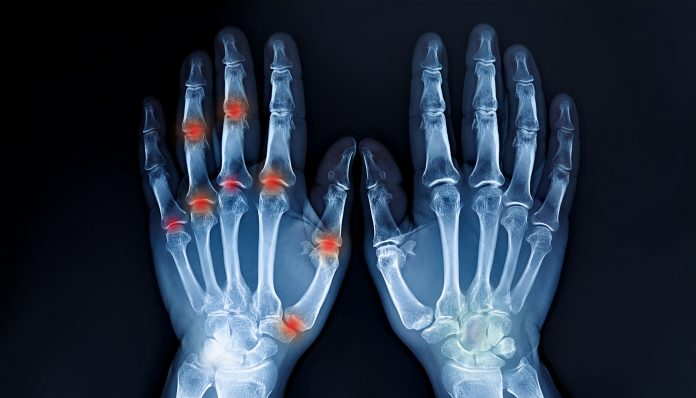

U današnjem članku govori se o životnom iskustvu jedne žene iz Cazina koja je godinama patila od reume i trnjenja ruku.

- Njena borba trajala je dugo i bila je ispunjena bolovima, neprospavanim noćima i bezuspješnim pokušajima da pronađe rješenje kroz klasičnu medicinu. U trenucima kada bi bolovi bili najjači, često se budila jer nije mogla pomjeriti prste ili bi joj predmeti ispadali iz ruku. Lijekovi koje su joj ljekari propisivali davali su tek kratkotrajno olakšanje, ali nikada nisu donijeli trajno poboljšanje. Upravo tada odlučila je da posluša savjet starije žene iz svog komšiluka i pruži šansu prirodnom receptu koji će joj promijeniti život.